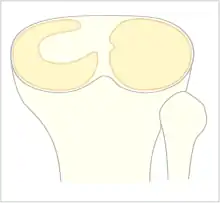

Le ménisque normal a une forme de croissant fin. Dans le cas du ménisque discoïde il existe un épaississement du ménisque pouvant aller d'une forme en croissant épais jusqu'à une forme de disque recouvrant le plateau tibial.

La classification de Watanabe décrit trois types de ménisque discoïde selon le degré de couverture du plateau tibial et selon l'attache postérieure du ménisque : ménisque discoïde complet, incomplet et variant-ligament de Wrisberg[1],[2].

Le ménisque discoïde complet recouvre totalement le plateau tibial externe (type I)[2]. Le ménisque discoïde incomplet (type II) ne le recouvre qu'incomplètement[2]. Dans le cas du variant-ligament de Wrisberg, il n'existe pas de frein méniscal postérieur[2].